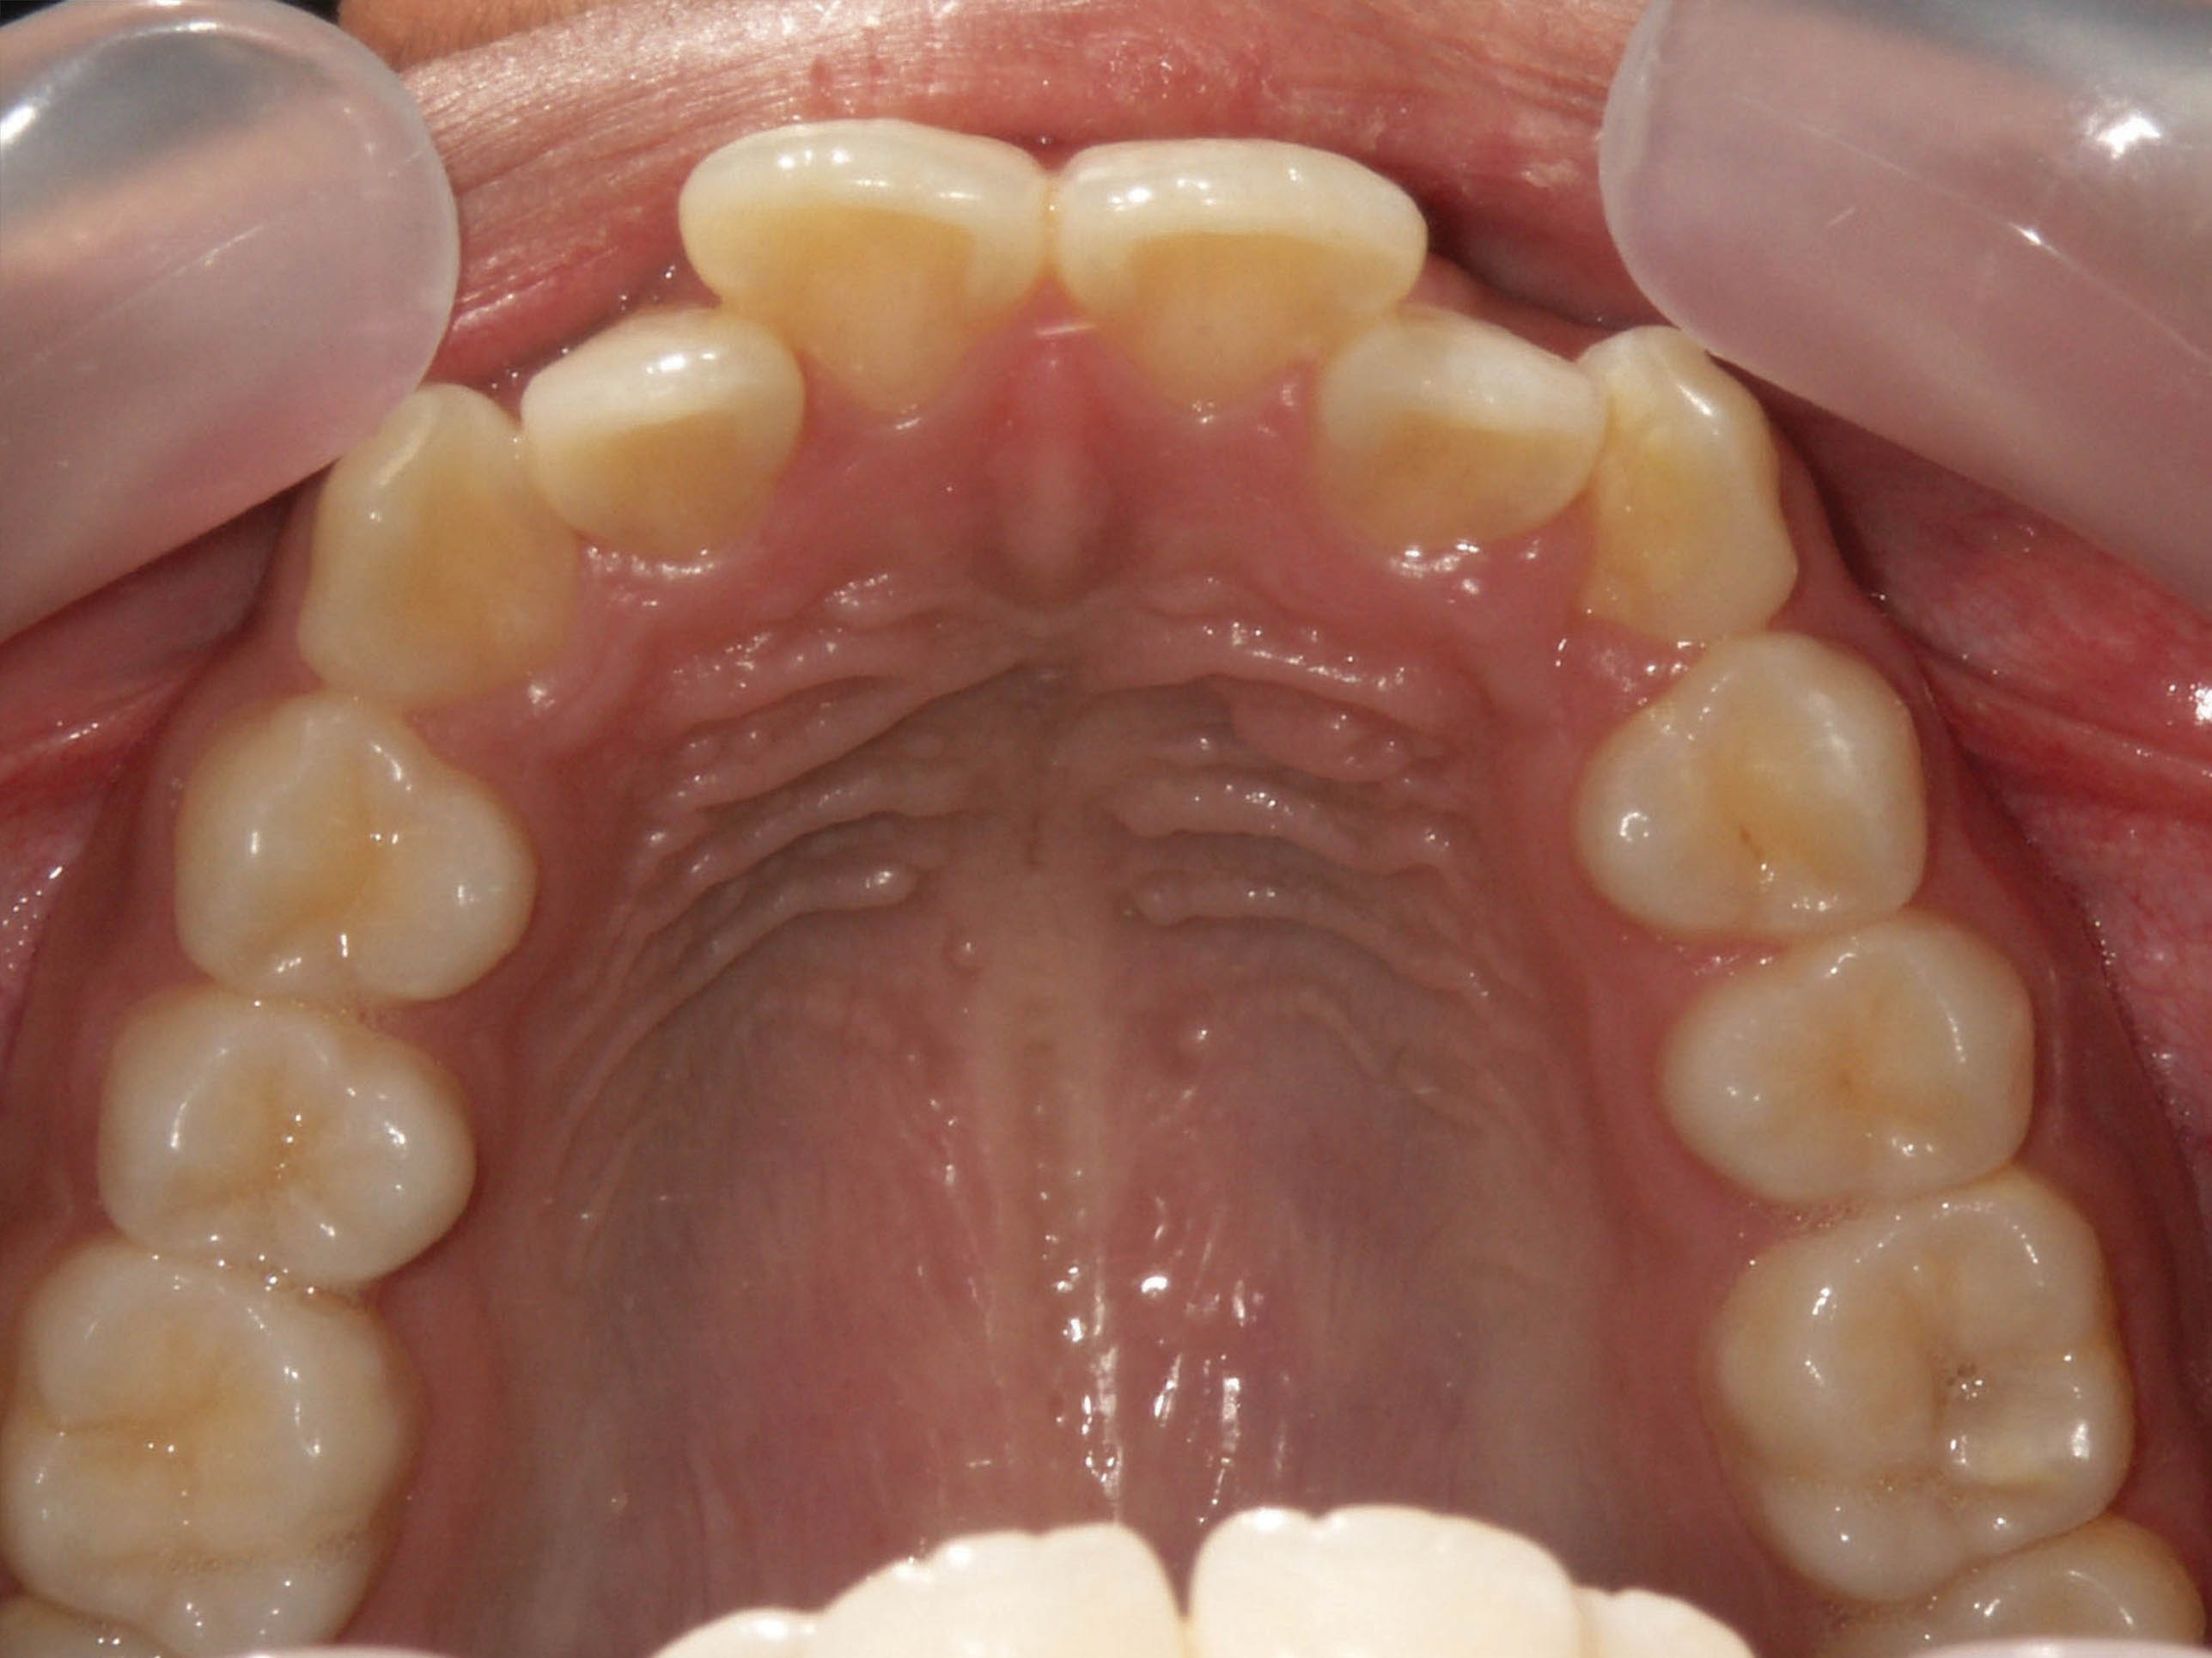

بعد از درمان